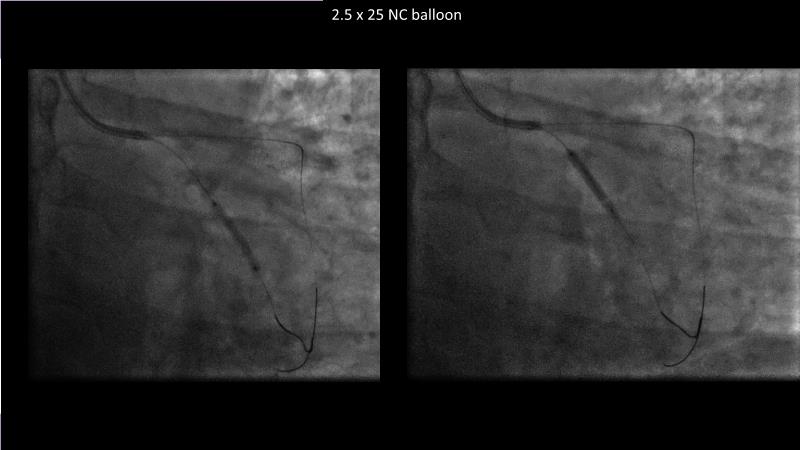

Consult this session to understand the technology and scientific evidence of the novel sirolimus drug-coated balloon, to learn its utility for PCI in a variety of lesion and patient subsets and to understand the evidence and outcomes in real-world patients.

- To learn the utility of the DCB for PCI in a variety of lesion and patient subsets